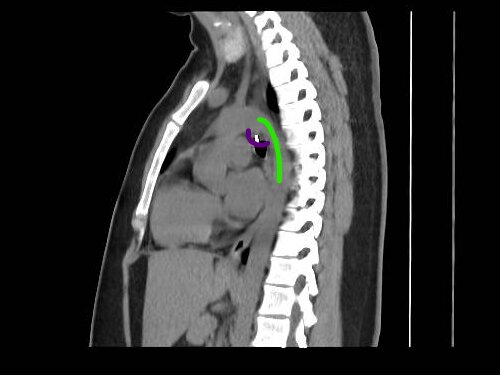

The metallic object was located just half a millimetre from her aorta artery, the body’s main blood highway.

A radiologist told her that the ring was positioned dangerously close to her aorta artery.

“It was only 0.5 millimetres from my aorta.